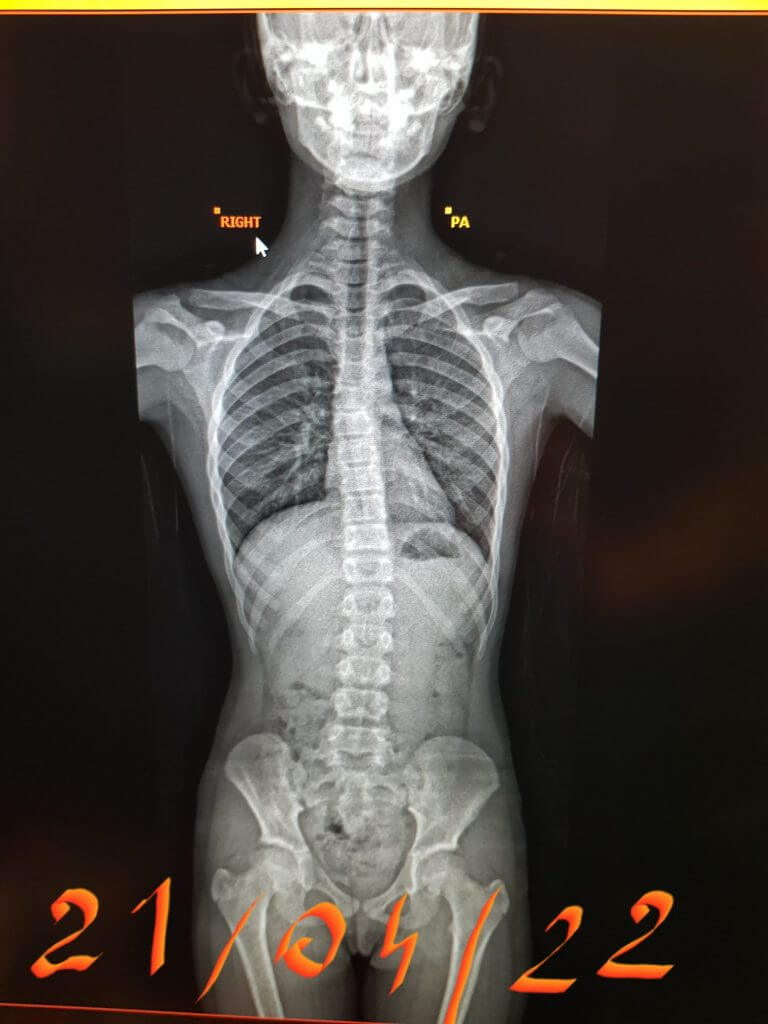

This patient has been seen by ScoliosisUK ltd Physiotherapist since 2013 when the patient was just 6 years old. This is not an idiopathic case – this is a non-idiopathic case – the cause is thought to be a post-operative rib fusion on the right side causing a large left thoracic curve on the left. The original cobb angle was around 50 degrees, and the family were desperate for this patient, who already had complex surgery as an infant, obviously wanted to avoid growing rods or fusion. This patient was provided with a NHS Boston and Cheneau derivatives initially and then finally several Gensingen Cheneau brace from 2016 and has managed to avoid surgery – now she is 15 years old with a 35-degree thoracic cobb angle. It’s been a tricky case as the consultant surgeon did not want to separate the ribs, which would have allowed for more cobb angle correction as the fusion of ribs prevents this, but this girl is a fighter, and she is now becoming a thriving young woman. She has had sharp bursts of support Schroth Best Practice home programs over the years in 6-12 week amounts to help with her shortened muscles and scar tissue, mum and dad both supportive. Her final Gensingen brace is being fitted shortly and we hope to see further signs of maturity on her X-ray to allow for part time hours this year, we all have everything crossed to see bony maturity and allow more weaning from brace sometime soon.

‘Non-idiopathic case – 6-year-old juvenile scoliosis thought to be a consequence of previous surgery and ultimately ribs fusing together. She reversed the curve from above 50 to 39 degrees cobb angle and holding strong at age 15’